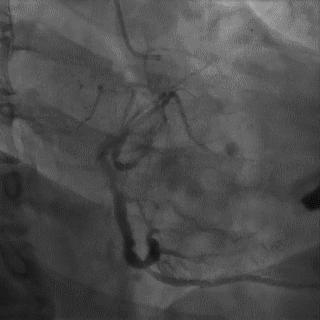

(4)LIMA桥血管造影

首选导管:JR4.0导管

其他导管:如果开口明显成角应选用专用的内乳动脉造影导管

➢ CASE 6

经股动脉途径TIG,非选择造影如果能清晰显影,可不做超选造影

➢ CASE 7

经左侧桡动脉途径JR4.0,非选择造影如果能清晰显影,可不做超选造影